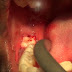

- Formation of pus, which can be seen exuding from beneath the operculum (i.e. a pericoronal abscess), especially when pressure is applied to the operculum.

- Signs of trauma on the operculum, such as indentations of the cusps of the upper teeth, or ulceration. Rarely, the soft tissue around the crown of the involved tooth may show a similar appearance to necrotizing ulcerative gingivitis.